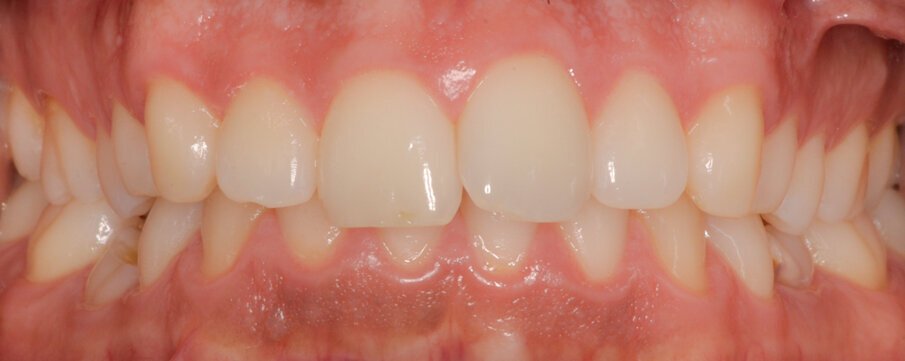

Fig. 18_Restauri defintivi.